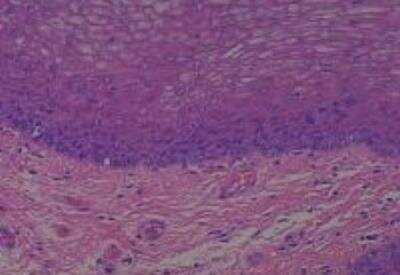

Hematoxylin & Eosin Stain: Human Common Tissue MicroArray (Normal Adjacent) [NBP2-30215] - 103. Stomach